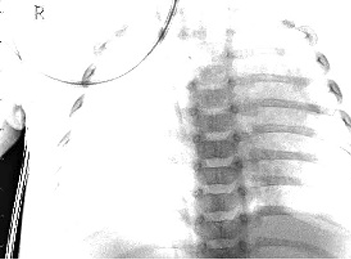

Table 6 Fused image output.

From: Multimodal medical image fusion combining saliency perception and generative adversarial network